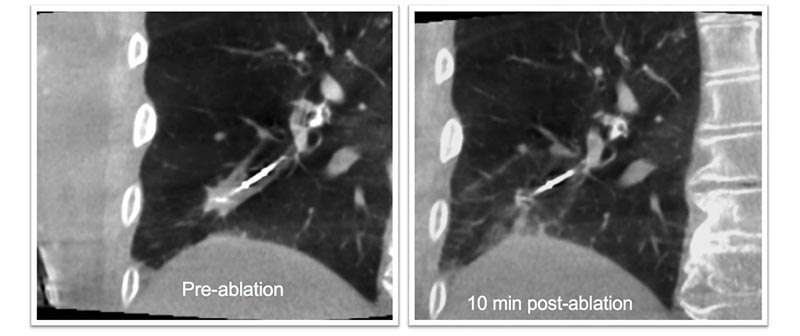

La plataforma Azurion Lung Suite está diseñada para procediemientos de broncoscopia, lo que ayuda a los médicos a realizar biopsias endobronquiales y extirpación de lesiones durante el mismo procedimiento.

Al permitir el examen de áreas de los púlmones que sólo se podían revisar de manera invasiva con un método menos doloroso para los pacientes es posible tener un diagnóstico más preciso y en algunos casos hasta realizar el tratamiento el mismo día en que se hace el diagnóstico, lo que da más tiempo a los pacientes para atenderse debidamente contra el cáncer de pulmón.